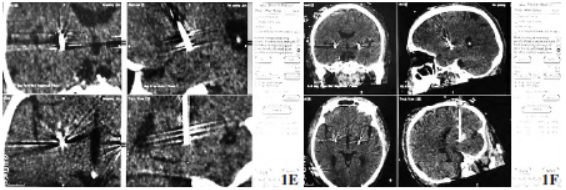

图1Gpi-DBS治疗痉挛性斜颈;1A术前左侧靶点轴位MRI定位;1B术前右侧靶点轴位MRI定位,箭头所指红点处;1C术中右侧Gpi电生理信号;1D术中左侧Gpi电生理信号,箭头为Gpi核团电信号,呈爆发性、不规则的高频放电;1E术后CT右侧电极与靶点融合;1F术后CT左侧电极与靶点融合

在典型电信号处分别置入(Medtronic3387-40)电极并安装临时体外刺激器。术后复查颅脑CT,与术前计划进行融合(图1),确认电极位置无偏移,观察无针道出血等严重并发症。术后即开启临时刺激器观察效果及不良反应,刺激参数设定为左侧Gpi:触点1-、2-、3+;右侧Gpi:触点8-、9-、10+;电压4.0V,频率180Hz,脉宽90μs。病人大部分症状较术前明显好转。但出现言语不清、构音障碍

肌、肩胛提肌、斜方肌较右侧肥厚。病人自诉用手提捏颈部肌肉,症状可暂时好转。评估无明显手术禁忌证,于全麻监护下行MRI扫描。采用全麻+术中唤醒麻醉,术前全麻下安装Leksell-G型脑立体定向框架(瑞典,Elekta),行颅脑CT扫描后数据导入framelink5.4.0(美国,Medtronic)计划系统与MRI图像融合,选择苍白球内侧部(globus pallidus internus,Gpi)为手术靶点。